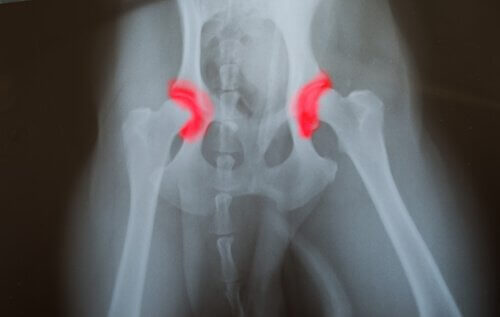

Hvad er dysplasi?

Hofte- eller albuedysplasi er en arvelig sygdom, som går fra generation til generation. Det er forårsaget af knoglerne, der danner et led – enten ved hoften eller albuen – som ikke er placeret eller justeret korrekt. Dette får dem til at gnide mod hinanden og lave forkerte bevægelser.

Dette forårsager et fremskyndet slid, hvilket forårsager andre problemer, som kan føre til malfunktion af ledene. Problemet med denne sygdom er, at den er stille.

Det betyder, at problemet kan have eksisteret i lang tid, endda siden fødslen, men dyret vil ikke føle nogen smerte, indtil de senere stadier i livet. Du vil bemærke det, fordi dit kæledyr vil gå fra at spise og hoppe til næsten ikke at være i stand til at bevæge sig overhovedet.